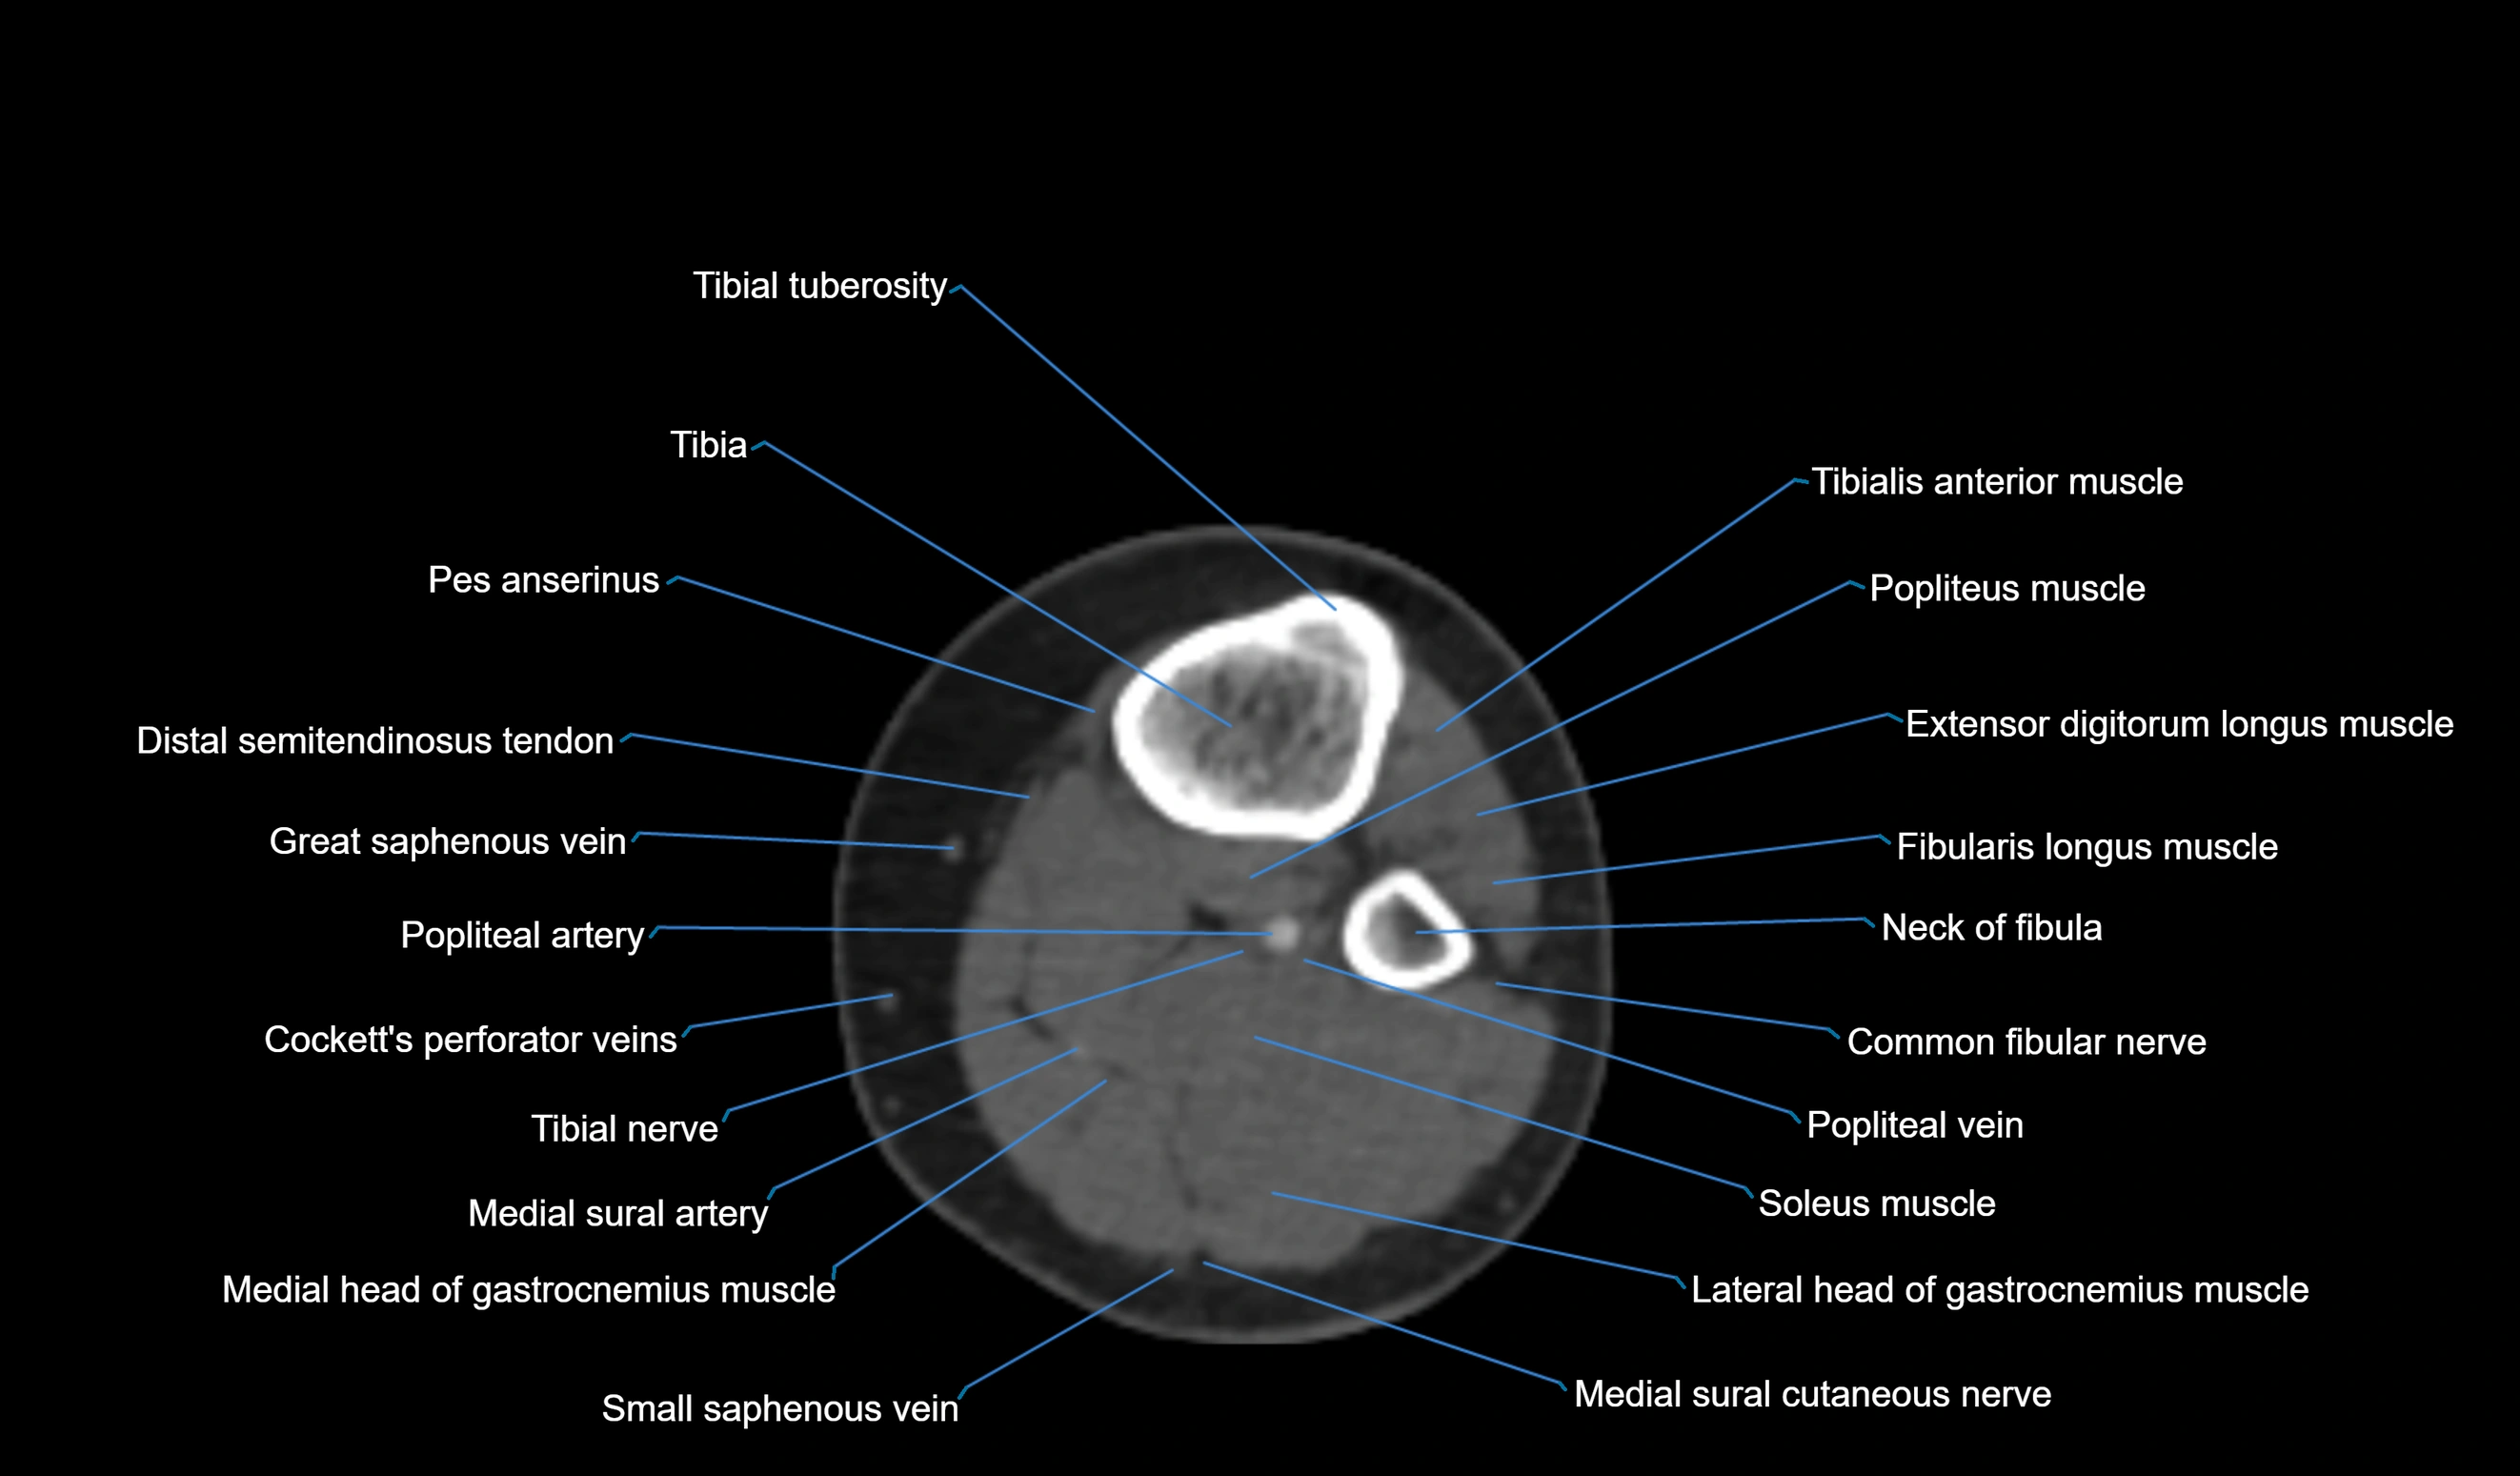

CT image